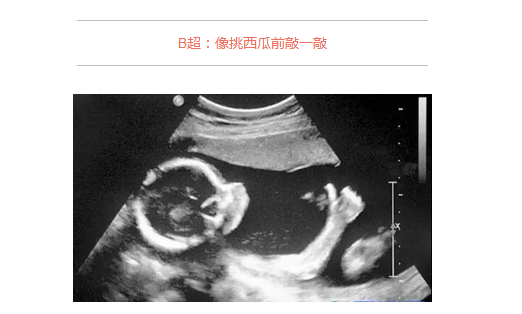

B超的原理是用超声波穿透人体,当声波遇到人体组织时会产生反射波,通过计算反射波成像。就像挑西瓜一样,边敲边看显示病灶情况。